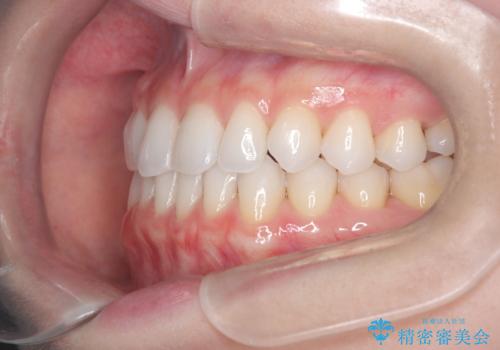

【インビザライン】前歯の凸凹をマウスピース矯正でなおしたい

- 前歯の凸凹を主訴に来院されました。

上の前歯は翼状捻転と呼ばれる状態でしたが、奥歯の遠心移動を行うことで配列スペースを確保することで綺麗に歯を並べることができました、

途中でインビザラインの使用時間が短くなってしまったため期間が予定より少し伸びましたが、1年半で満足いく結果となり患者様に喜んでいただけました。

下顎骨が右側に偏位していることにより下顎前歯の真ん中はずれています。